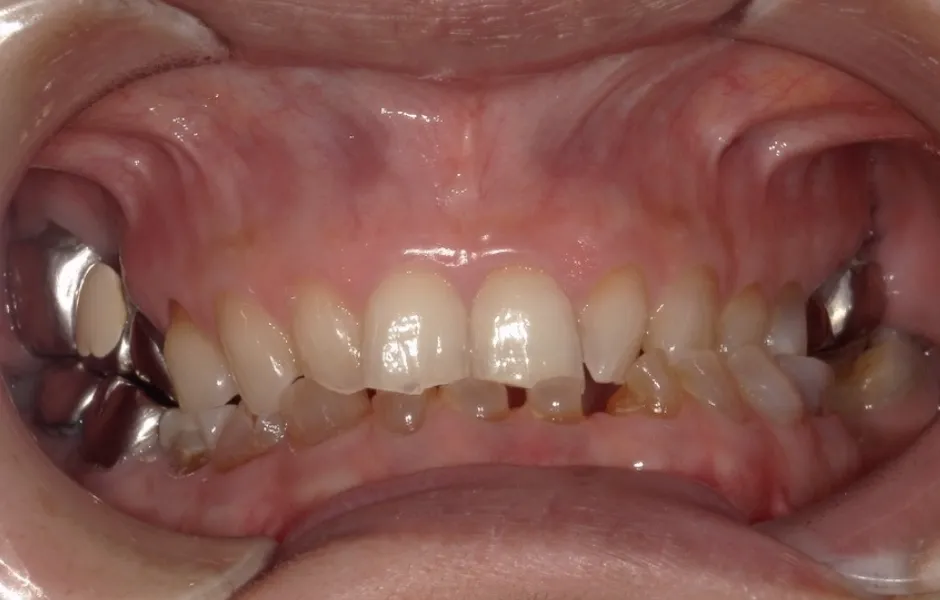

全顎治療・咬合治療

(歯がボロボロ)虫歯や歯周病が悪化して、歯を失っている・ボロボロのまま放置すると、機能性と審美性に影響がでます。お口のトラブルを改善できるよう、さまざまな治療をご提案します。